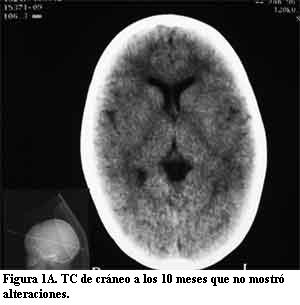

Niña de 10 años, sin antecedentes pre ni perinatales que a los 10 meses de edad, luego de un traumatismo de cráneo de intensidad leve, presentó crisis caracterizadas por vómitos, desviación óculo-cefálica a izquierda e hipotonía global, con sopor posterior, que se reiteraron en el curso de 24 horas. Su examen físico fue normal. En esa oportunidad se le realizó fondo de ojo, tomografía de cráneo (TC) (figura 1A) y electroencefalograma (EEG), que fueron normales. Evolucionó favorablemente hasta la edad de 4 años, cuando presentó nuevamente crisis epilépticas parciales complejas, con un episodio de status epilepticus. El EEG mostró signos de sufrimiento cerebral focal a nivel parieto-occipital izquierdo. En la TC se observó una imagen hiperdensa occipital izquierda (figura 1B). La resonancia magnética (RM) mostró un área de realce leptomeníngeo con el gadolinium en la misma topografía en relación con una corteza cerebral de aspecto atrófico, así como el plexo coroideo ipsilateral aumentado de tamaño (figura 2). En la angiorresonancia se observó una disminución de la señal de flujo en el seno venoso lateral izquierdo que se interpretó secundaria a trombosis (figura 3A). En la angiografía digital se comprobó que el seno venoso estaba permeable con un marcado enlentecimiento de la circulación compatible con estasis venosa y una alteración de la barrera hematoencefálica a nivel occipital izquierdo (figura 3B). Los anticuerpos antigliadina y antiendomisio fueron negativos. El estudio de los factores de la coagulación descartó una alteración protrombótica. Medicada con difenilhidantoína, reiteró crisis similares a las anteriores a los 6 años de edad. Desde el punto de vista neuropsicológico, su nivel intelectual fue catalogado como marginal. Luego de tres años sin crisis, a los 9 años presentó un episodio de breve duración caracterizado por cefalea intensa y alteración de la conciencia. En la exploración neurológica se comprobó que presentaba una discreta paresia de miembro superior derecho. Una nueva TC mostró un significativo aumento de las calcificaciones occipitales izquierdas (figura 1C).

La presencia de un angioma facial congénito con las características antes mencionadas es el signo principal que orienta hacia el diagnóstico en el SSW clásico (1,3,7,16). Como las otras manifestaciones clínicas pueden ser relativamente inespecíficas, cuando el paciente no presenta las lesiones cutáneas típicas, el diagnóstico de angiomatosis leptomeníngea se basa fundamentalmente en los hallazgos neuroimagenológicos. Las primeras manifestaciones clínicas de este caso clínico fueron sus crisis epilépticas parciales a los 10 meses de edad pero en ese momento, el examen físico y la TC fueron normales. A los 4 años, cuando reiteró crisis epilépticas, se observaron las calcificaciones occipitales izquierdas en una nueva TC. La RM con gadolinium mostró las imágenes típicas de la angiomatosis pial con un área de realce leptomeníngeo a nivel parieto-occipital izquierdo, en relación con una corteza cerebral de aspecto atrófico, así como el plexo coroideo ipsilateral aumentado de tamaño. Se realizó una angiorresonancia en la cual se observó una disminución de la señal de flujo en el seno venoso lateral izquierdo que se interpretó como secundaria a trombosis. Sin embargo, la angiografía digital realizada tres días después, mostró que el seno venoso estaba permeable y que presentaba un marcado enlentecimiento de la circulación compatible con estasis venosa. Posteriormente, a los 9 años, una nueva TC mostró un significativo aumento de las calcificaciones occipitales, persistiendo la imagen del plexo coroideo aumentado de tamaño. Esta serie de estudios imagenológicos es enteramente compatible con el diagnóstico de angiomatosis leptomeníngea (1,6,8,10,13-18).

Existen pocos estudios publicados que describan la evolución clínica e imagenológica de los pacientes con SSW (22). Si bien en la literatura se menciona la progresión de las calcificaciones, no es habitual que la misma se haya documentado como en este caso, desde la tomografía normal obtenida a los 10 meses de vida, a la observación de las calcificaciones a los 4 años y la comprobación del significativo aumento de las mismas a los 9 años de vida. Es interesante destacar la discordancia existente entre la evolución de la epilepsia de esta paciente durante sus primeros 10 años de vida, que ha sido aceptablemente controlada, y la significativa progresión de las lesiones encefálicas objetivadas en el aumento de las calcificaciones en el seguimiento tomográfico.

La interpretación de los estudios angiográficos realizados en esta paciente es otro de los aspectos interesantes de este caso clínico. Aunque la disminución de la señal de flujo en el seno venoso lateral izquierdo en la angiorresonancia fue inicialmente interpretada como secundaria a una trombosis, es probable que dicha imagen se correspondiera a enlentecimiento del flujo y que el seno venoso estuviera permeable, como se observó en la angiografía digital (18).